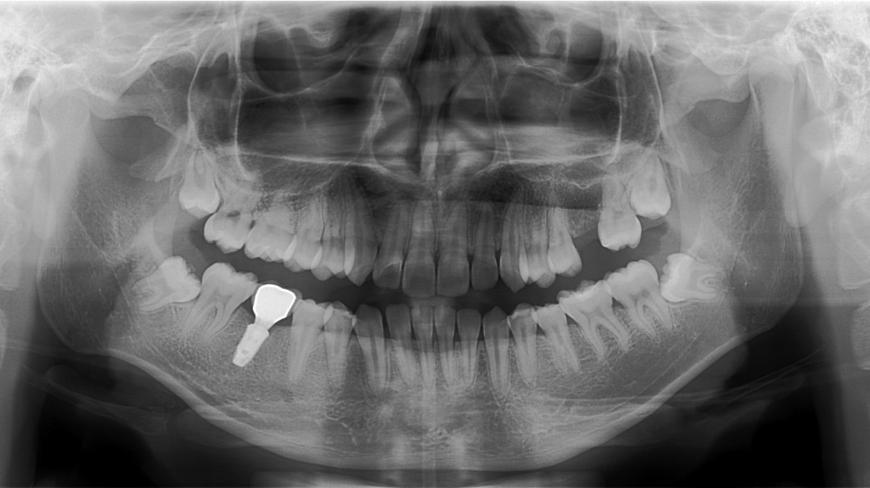

Răng implant là phương pháp phục hồi răng đã mất bằng cách cấy một trụ titanium vào xương hàm, sau đó gắn mão răng lên trụ đó. Thời gian sử dụng của răng implant thường kéo dài từ 10-20 năm hoặc thậm chí lâu hơn, nhưng điều này còn phụ thuộc vào một số yếu tố sau:

- Chất lượng và số lượng xương hàm : Implant sẽ chỉ bền nếu có đủ xương hàm khỏe mạnh để hỗ trợ trụ. Trong một số trường hợp, nếu xương hàm không đủ dày hoặc không khỏe, bác sĩ có thể phải thực hiện phẫu thuật ghép xương trước khi cấy implant.

- Chất liệu của trụ và mão răng : Trụ implant thường được làm từ titanium hoặc zirconium, hai chất liệu có độ bền cao. Mão răng có thể làm từ các vật liệu như sứ, composite hay kim loại, tùy thuộc vào yêu cầu thẩm mỹ và tài chính của từng người.